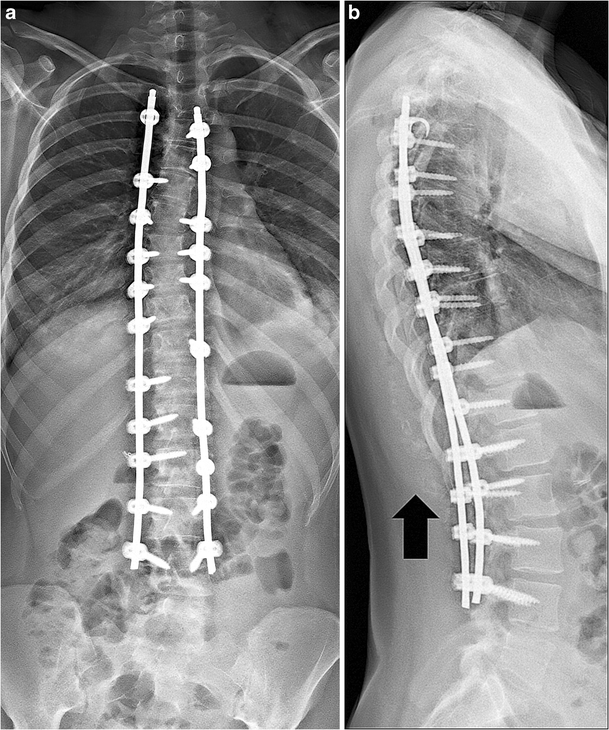

From scoliosistexas.com

Flatback Syndrome Scoliosis Texas Titanium Rods In Back For Scoliosis The authors conducted the first many things need to be considered when planning surgery for scoliosis. This article provides answers to common questions. six magec rods were removed unexpectedly early due to black staining of the skin, swelling or. scoliosis rod surgery, also known as spinal fusion or growing surgery, is a way to help kids with. Titanium Rods In Back For Scoliosis.

From link.springer.com

Pediatric spine imaging post scoliosis surgery SpringerLink Titanium Rods In Back For Scoliosis many things need to be considered when planning surgery for scoliosis. The authors conducted the first This article provides answers to common questions. scoliosis rod surgery, also known as spinal fusion or growing surgery, is a way to help kids with serious curves in. also known as spinal fusion, scoliosis surgery commonly involves the use of titanium. Titanium Rods In Back For Scoliosis.